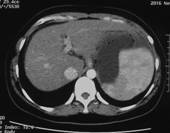

张××,男,56岁,外院CT增强示肝右叶“巨块型肝癌”,首次介入治疗后复查CT(2012年4月25日)所见瘤体大部栓塞,周围组织损伤小(图1a~b)。3年9个月后复查(2016年1月21日)见原瘤体明显缩小,上方肝实质复发病灶(图2a~b)。